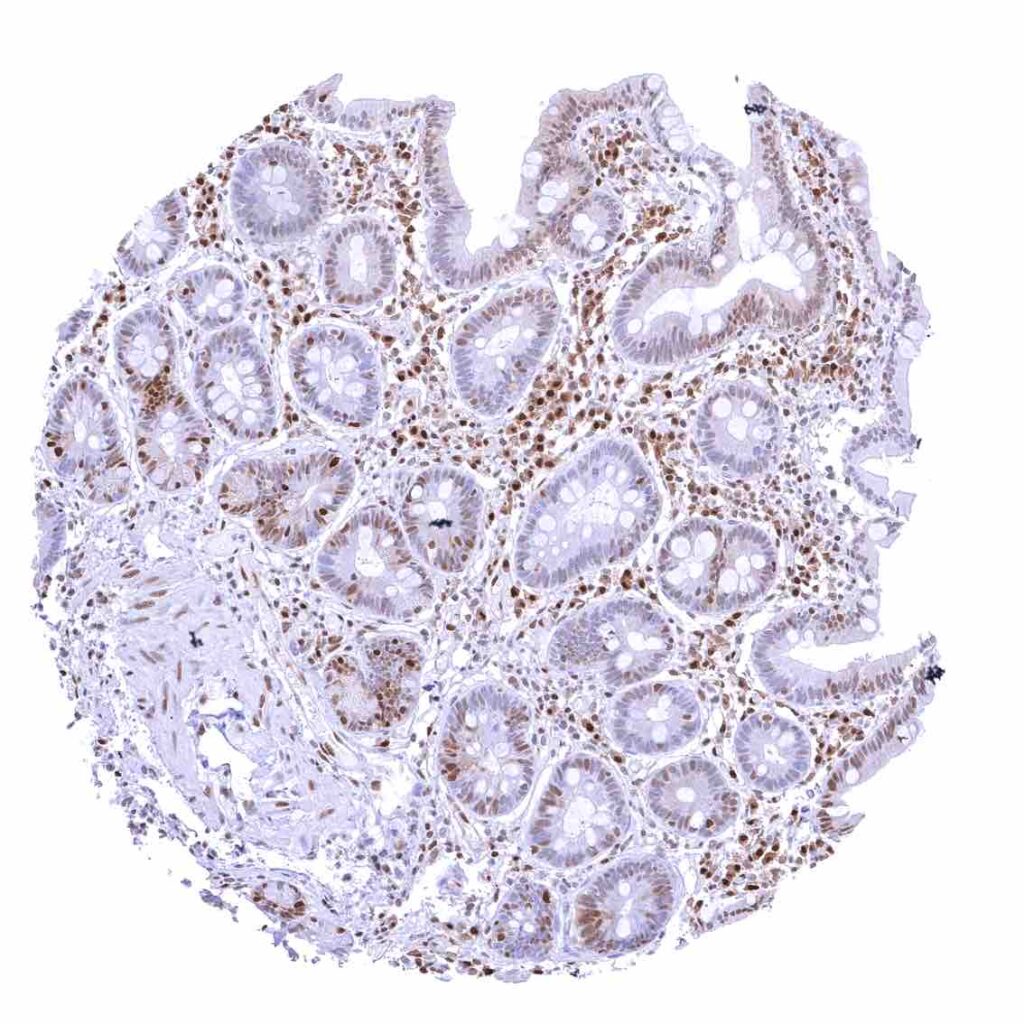

Appendix, mucosa – Among epithelial cells, nuclear p27 staining predominates in superficial epithelial cells. Most p27 staining occurs in lymphatic cells, however.